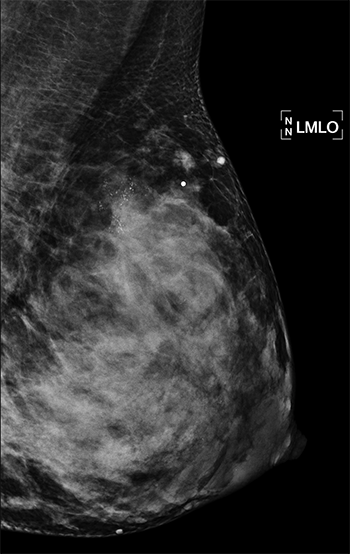

Breast imaging during pregnancy and lactation is already challenging due to both physiologic and structural changes to the breast. In addition, the American College of Radiology (ACR) reports that “Pregnancy-associated breast cancer (PABC) is increasing as more women delay child bearing into the fourth decade of life, and imaging of clinical symptoms should not be delayed.” At this time, guidelines from the American College of Radiology (ACR) recommend ultrasound as the first-line imaging modality for the evaluation of palpable masses in pregnant and lactating women, but data regarding breastfeeding women age 30 years and older are near nonexistent.

With this in mind, a team of breast imaging radiologists from the UC San Francisco Department of Radiology and Biomedical Imaging and the Mayo Clinic Department of Radiology set out to evaluate the diagnostic performance of targeted ultrasound as the primary imaging modality for the evaluation of palpable masses in lactating women, including those of advanced maternal age. Their second aim was to evaluate the added benefit of mammography.

Co-authors analyzed data from 167 symptomatic, breastfeeding women—at an average age of 35—who underwent targeted ultrasound. They found that ultrasound scored high marks, sensitivity and specificity of 100 percent and 70 percent respectively. Positive predictive value of an abnormal examination and positive predictive value of biopsy were 9.4 percent and 10 percent, respectively. In those who underwent mammography in addition to US, mammography added seven false-positive findings without additional cancer diagnoses. Specificity was lowered with the addition of mammography from 67 percent to 61 percent. These results support US as the primary modality for the evaluation of palpable lumps in breastfeeding women. You can read the full methodology of this study, which is the largest to date, in Radiology.